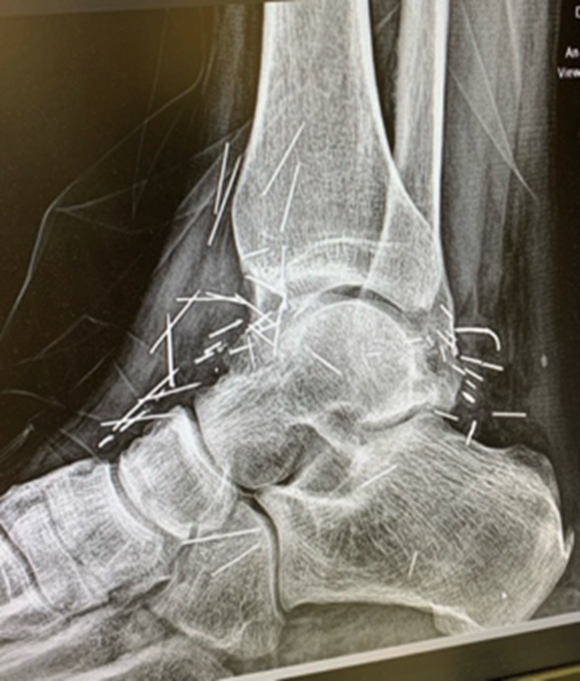

On physical exam, one could note small scars and palpable foreign bodies along the anterior, lateral, and medial aspects of the ankle joint with decreased range of motion and decreased sensation along lateral leg and foot. Of note, Tinel’s and Valleix’s signs were negative at the ankle, which we feel was likely secondary to neuropraxia at a more proximal level.

X-ray imaging revealed numerous needle-like metallic foreign bodies. We prescribed gabapentin and ordered electromyography/nerve conduction velocity (EMG/NCV) studies. These studies revealed evidence of left peroneal neuropathy, most commonly seen at the fibular head. The study also noted increased duration, increased amplitude, and decreased recruitment in the left posterior tibial, peroneus longus and extensor hallucis longus muscles. The patient found little relief with conservative measures.